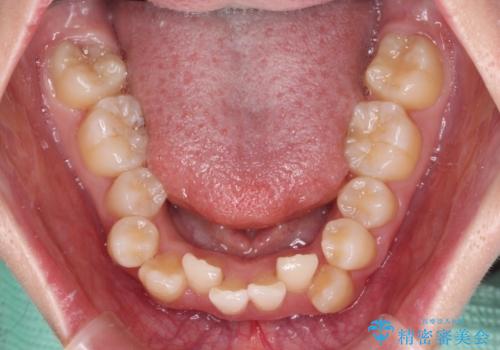

- 上下前歯の八重歯やデコボコと、唇の閉じにくさを気にして来院された患者様です。

口元の突出感を改善するため、上下左右の第一小臼歯4本を抜歯し、ワイヤー装置にて矯正治療を行うこととしました。